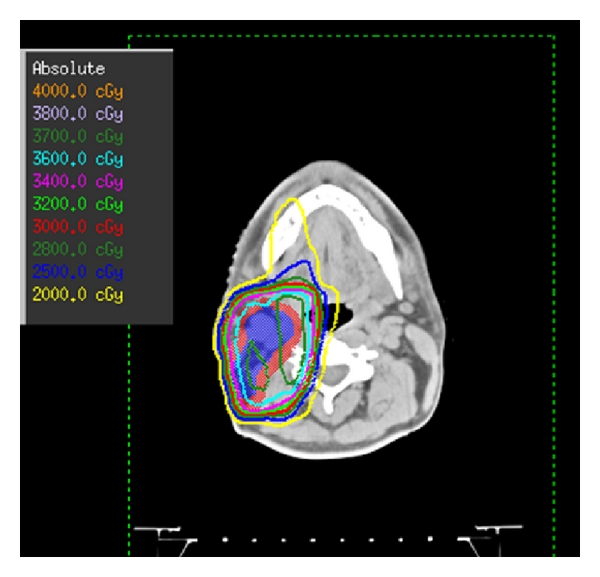

An INRT started in January 2012 and delivered 36 Gy within 18 fractions using conformational technique (Figure 3).